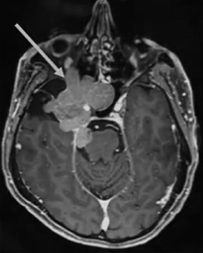

2012年,53岁的Leo突然发现自己嗅觉减退、视力下降时,就医检查发现右侧梅克尔腔脑膜瘤,随即进行了手术。谁能想到7年过后,脑膜瘤再次卷土重来,出现严重的V1(嗅神经)、V2(视神经)和V3(动眼神经)感觉减退和疼痛,症状比第一次手术前还要严重。磁共振成像(MRI)显示肿瘤大面积复发,延伸至海绵窦(CS)、后颅窝(PF)、蝶窦(SS)、翼腭窝(PPF)和颞下窝(ITF)。这个张牙舞爪的肿瘤,属实不太容易切除。

患者术前影像。(A)术前轴位T1加权钆增强磁共振成像(MRI),显示脑膜瘤延伸至后颅窝、海绵窦、眼眶和蝶窦。(B)肿瘤延伸至中颅窝、翼腭窝和颞下窝。(C)术前轴位计算机断层扫描(CT)显示蝶骨大翼侵蚀和蝶窦受累。